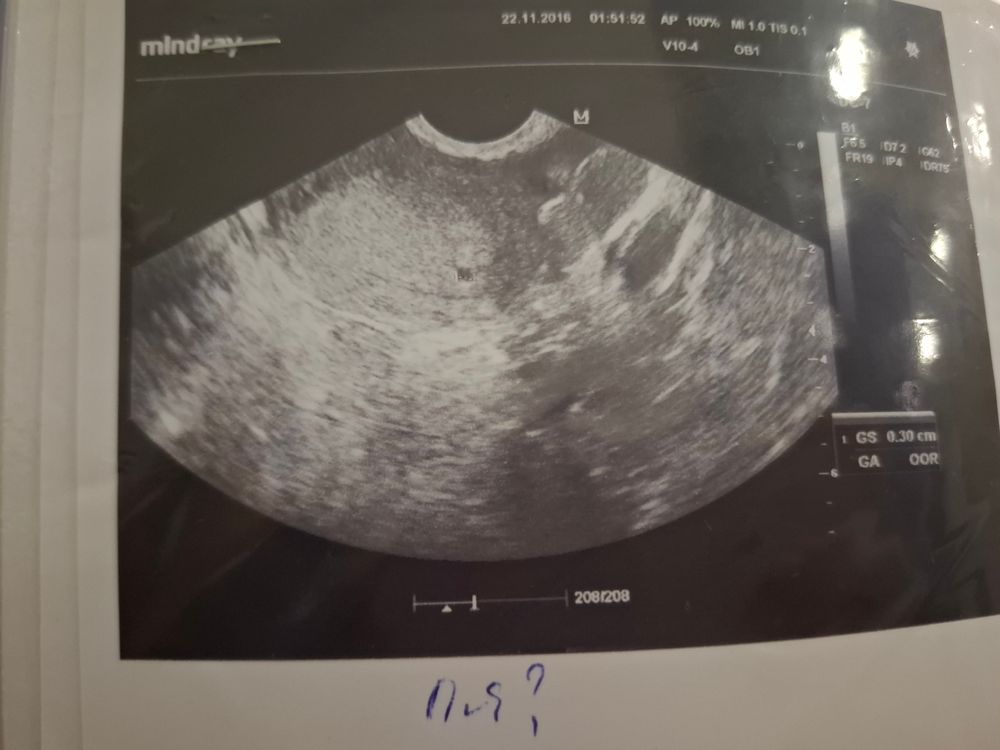

2недели тянет с левой стороны.. Была на узи, в заключении жидкость в полости и образование около 5-10мм, а какое именно образование-непонятно,(было в понедельник) была у врача в тот же день, сказала ждать месячных, если придут значит нужна будет чистка, если нет, то это непонятное образование есть беременность. Сегодня утром сделала тест 2ярких полоски, задержка 1день только..Следующий прием 12декабря Переживаю жутко

У меня так было, тянуло один из яичников, я пошла на узи проверить не киста ли это (у меня 2 апоплексии в анамнезе), по узи кисты нет, много газов в кишечнике, жидкость в позадиматочном пространстве и образование 3 мм в полости матки. Сказали сделать тест, если положительный то это пя. Пришла домой там 2 полоски) сейчас с этим образованием сидим пазл собираем))

Айгуль Валиуллина, мне сказали что была бурная овуляция и видимо жидкость не успела рассосаться. Даже узи для вас нашла)